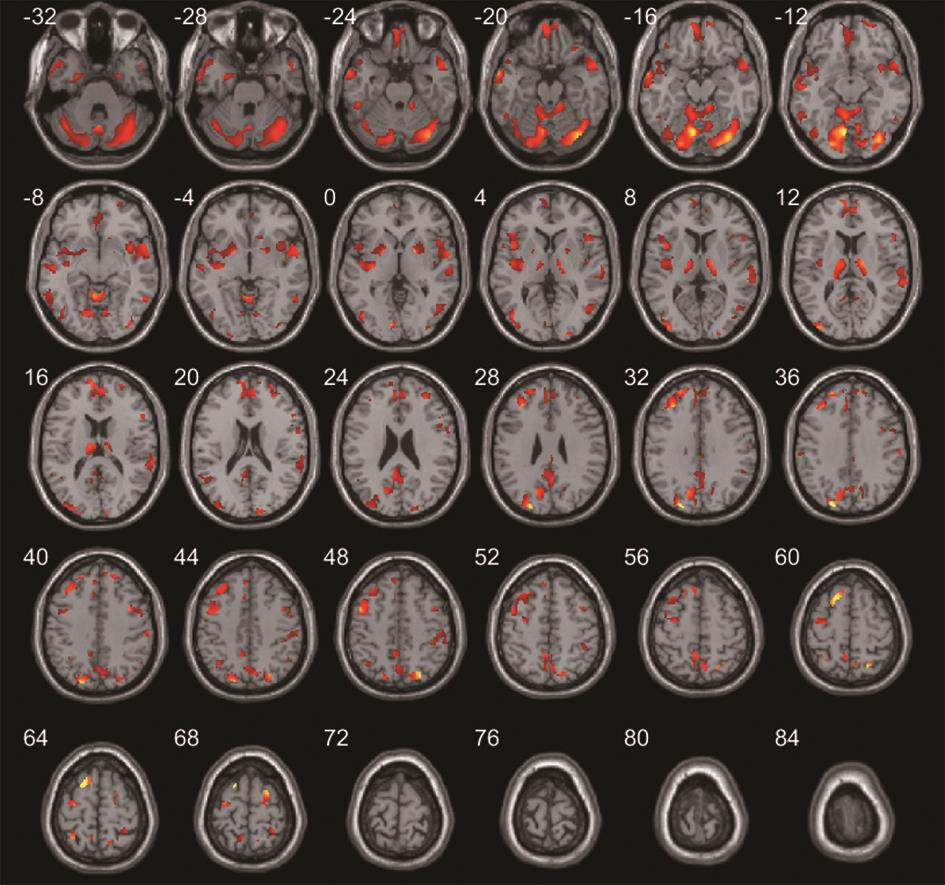

• 正常成人与伴吞咽障碍的急性脑梗死患者吞咽相关脑功能区激活机制的血氧水平依赖功能磁共振研究

2022, 47(7):802-810. DOI: DOI:10.13406/j.cnki.cyxb.003057

摘要:目的 运用血氧水平依赖功能磁共振(blood oxygenation level dependent-functional magnetic resonance imaging,BOLD-fMRI)技术对伴吞咽功能障碍的急性脑梗死患者和正常成人在吞咽活动时相应的脑功能区域激活特点进行研究,探索急性脑梗死患者吞咽功能障碍恢复过程中相关的脑功能区域调控方式。方法 选取2018年7月至2021年7月在昆明医科大学附属延安医院住院的伴吞咽障碍的急性脑梗死患者150例和正常成人100例,对其进行BOLD-fMRI扫描,记录两者在吞咽活动时相关脑功能区域的激活体积和强度,并对比两者间的差异。结果 共收集病例组150例,其中右侧脑梗死组患者50例,男29例,女21例,平均年龄(56.22±7.33)岁;左侧脑梗死组患者100例,男61例,女39例,平均年龄(58.07±6.84)岁;对照组100例,男57例,女43例,平均年龄(53.56±11.41)岁。对照组吞咽活动时激活的相关脑功能区域特点显示:两侧初级运动皮层中枢(BA4区)、运动前区/辅助运动区(BA6/8区)、缘上回(BA40区)、岛叶(BA13区)、颞上回(BA22区)、扣带回皮层(BA24区)、额叶内侧面(BA32区)、延髓、脑桥、基底核团、丘脑、小脑及左侧颞极(BA38区)和右侧颞横回(BA41区)等脑功能区激活体积和强度增加,左侧BA4区、BA40区、小脑激活体积较右侧大,差异有统计学意义(P<0.05);左右两侧脑区的激活强度差异无统计学意义(P>0.05)。右侧脑梗死病例组患者BOLD-fMRI扫描各脑区激活体积显示:右侧BA4区、BA6/8区激活体积较对照组减小,左侧BA6/8区、BA4区激活体积较对照组增大,双侧后扣带回皮层的BA23和顶叶内侧面BA31区体积较对照组增大,左侧视觉中枢的BA18/19和BA41区皮层激活体积较对照组增大,差异有统计学意义。右侧BA4区、BA6/8区、BA40区、BA13区激活强度较对照组降低,差异有统计学意义。左侧脑梗死病例组患者BOLD-fMRI扫描各脑区激活体积显示:左侧BA4区、BA6/8区的激活体积较对照组减小,右侧BA4区、BA6/8区激活体积较对照组增大,双侧BA23/31区、左侧BA41区、双侧BA7区、双侧BA18/19区和双侧小脑激活体积较对照组增大,差异有统计学意义。左侧BA4区、BA6/8区、BA40区、BA13区激活强度较对照组降低,差异有统计学意义。结论 双侧运动、运动前、感觉、嗅觉、听觉、脑干、小脑、基底核团等脑功能区均参与调控正常人的吞咽活动,且调控具有一定的偏侧性。同侧的运动功能区、运动功能前区激活体积降低,对侧运动功能区、运动功能前区激活体积增加是伴吞咽障碍的急性脑梗死患者吞咽相关脑功能区的主要代偿特点。